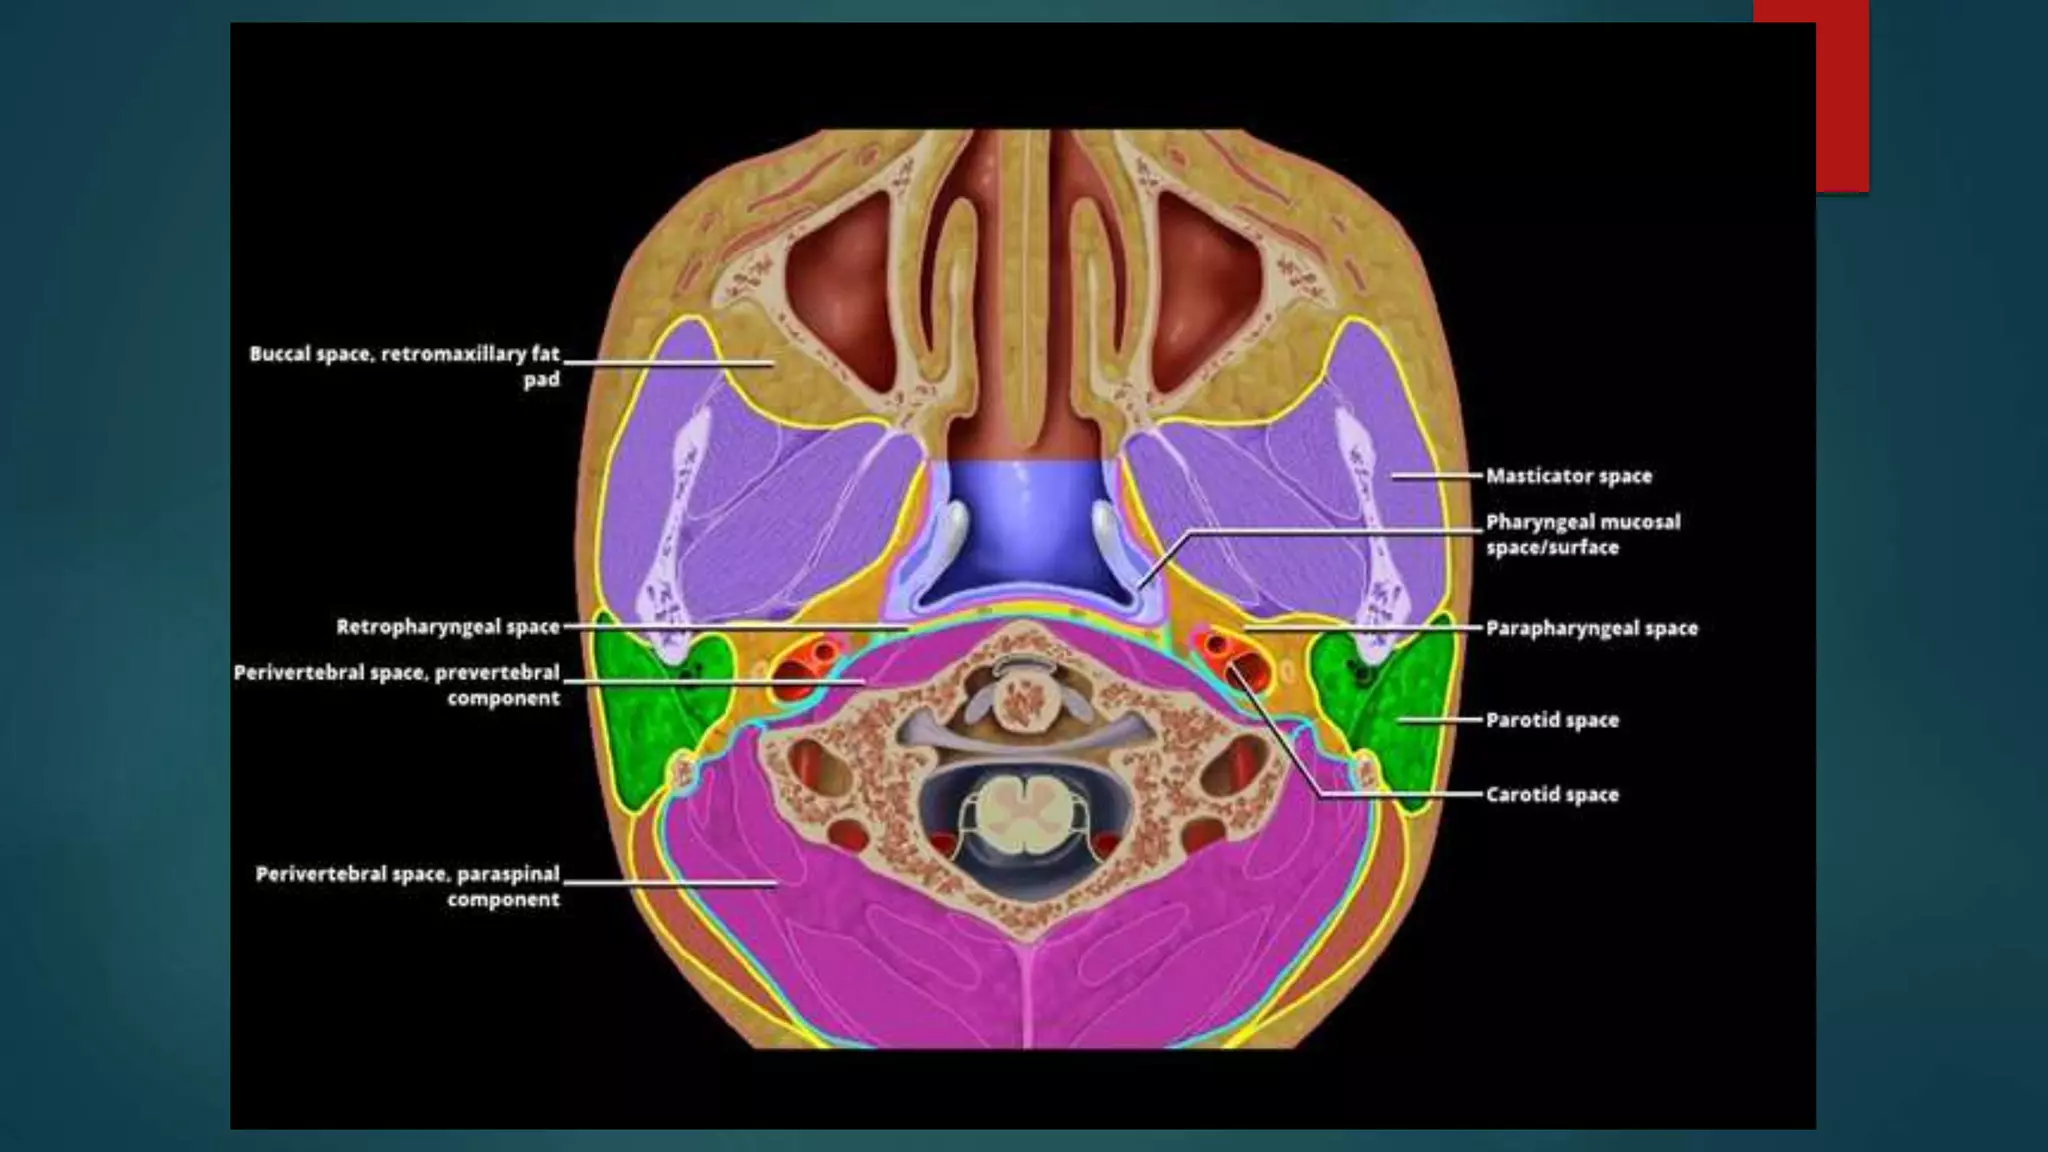

NECK SPACES

Described in relation to the hyoid bone.

 Suprahyoid Spaces.

 Infrahyoid Spaces.

 Spaces extending up to the entire length of the neck.

SUPRAHYOID SPACES

 Parapharyngeal Space

INFRAHYOID SPACES

PERIVERTEBRAL SPACE

 Posterior midline space of SHN and

IHN

 The perivertebral space is a

cylinder of soft tissue lying posterior

to the retropharyngeal space and

danger space surrounded by the

prevertebral layer of the deep

cervical fascia.

 Extent : base of skull to level of

coccyx

http://radiopaedia.org/articles/periverte

bral-space

 The deep cervical fascia sends a deep slip to the to the transverse

process which subdivides the space into:

• prevertebral portion: anteriorly located

• paraspinal portion: posteriorly located

 Contents:

CAROTID SPACE

 Paired tubular structure traversing SHN

and IHN

 Skull base to superior mediastinum

 Lateral to RPS

 Enveloped by carotid sheath : all 3

layers of DCf

 Contents : SHN – ICA IJV , CN9-12,

:IHN - CCA, IJV , CN10 trunk (

vagus)

 The bifurcation of the common carotid

usually occurs at the boundary of the

suprahyoid and infrahyoid spaces

MASTICATOR SPACE

 The masticator space are paired suprahyoid cervical spaces on each

side of the face. Each space is enveloped by the superficial (investing)

layer of the deep cervical fascia.

PHARYNGEAL MUCOSAL SPACE

 The pharyngeal mucosal space is the most internal compartment (closest

to the airway) of the seven deep compartments of the head and neck,

delineated by the middle (pretracheal) layer of deep cervical fascia . It

extends from the base of the skull to the cricoid cartilage.

PARAPHARYNGEAL SPACE

 The parapharyngeal space is shaped like

a pyramid, inverted with its base at the

skull base, with its apex inferiorly

pointing to the greater cornu of the hyoid

bone.